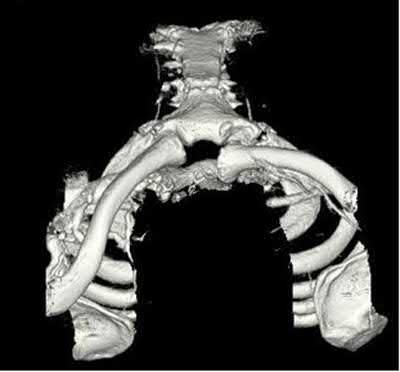

A 33-year-old secretary presents three months after a motor vehicle collision with a mild asymmetry to her sternal area and difficulty swallowing. She denies any complaints of respiratory distress or upper extremity paresthesias. Her upper extremity neurovascular exam shows no deficits. A 3-D computed tomography image is shown in Figure A. What is the most appropriate treatment for this patient?

The clinical presentation is consistent with a chronic sternoclavicular dislocation, which is defined as being greater than 3 weeks old. The 3D CT image shows posterior displacement of the medial clavicle relative to the sternum. Chronic anterior dislocations are recommended to be treated conservatively, especially if not symptomatic, but as this is a posterior dislocations, current recommendations are to treat them with reduction in order to avoid delayed issues with the medial clavicle interacting with the mediastinal structures.

The review article by Wirth and Rockwood notes the following complications with posterior dislocation: respiratory distress, venous congestion or arterial insufficiency, brachial plexus compression, and myocardial conduction abnormalities. They recommend reconstruction of the costoclavicular ligaments with resection of the medial claviclar head as needed for unstable or symptomatic injuries.